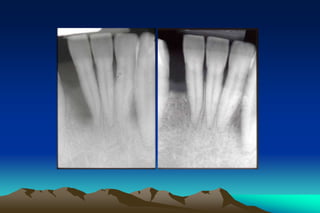

A common error in proximal instrumentation

is failing to reach mid-proximal region apical

to the contact point because this area is

relatively inaccessible and this technique

require more skill

A common errorin proximal instrumentation is failing to reach mid-proximal region apical to the contact point because this area is relatively inaccessible and this technique require more skill

• 51.